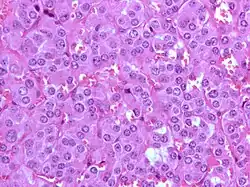

Feochromocytom je nádor z chromafinních buněk produkujících katecholaminy, které vyvolávají hypertenzi. Katecholaminy, které produkuje feochromocytom způsobují buď trvalou hypertenzi (vysoký krevní tlak), popřípadě epizody nebo záchvaty vážné hypertenze. Dalšími příznaky nadměrné produkce katecholaminů jsou bolesti hlavy, bušení srdce, pocení, nevolnost, úzkost a brnění v končetinách.

Přibližně 90% feochromocytomů je lokalizováno v nadledvinách. Ačkoliv některé jsou karcinomatózní povahy, většina je benigních – tedy nešíří se mimo danou lokalizaci, ale většina z nich dále roste. Pokud jsou ponechány bez léčby, symptomy se mohou zhoršovat tak jak tumor roste a po čase muže hypertenze zapříčiněná feochromocytomem poškodit další orgány, zejména srdce a ledviny; u pacienta se zvyšuje riziko infarktu nebo mrtvice.